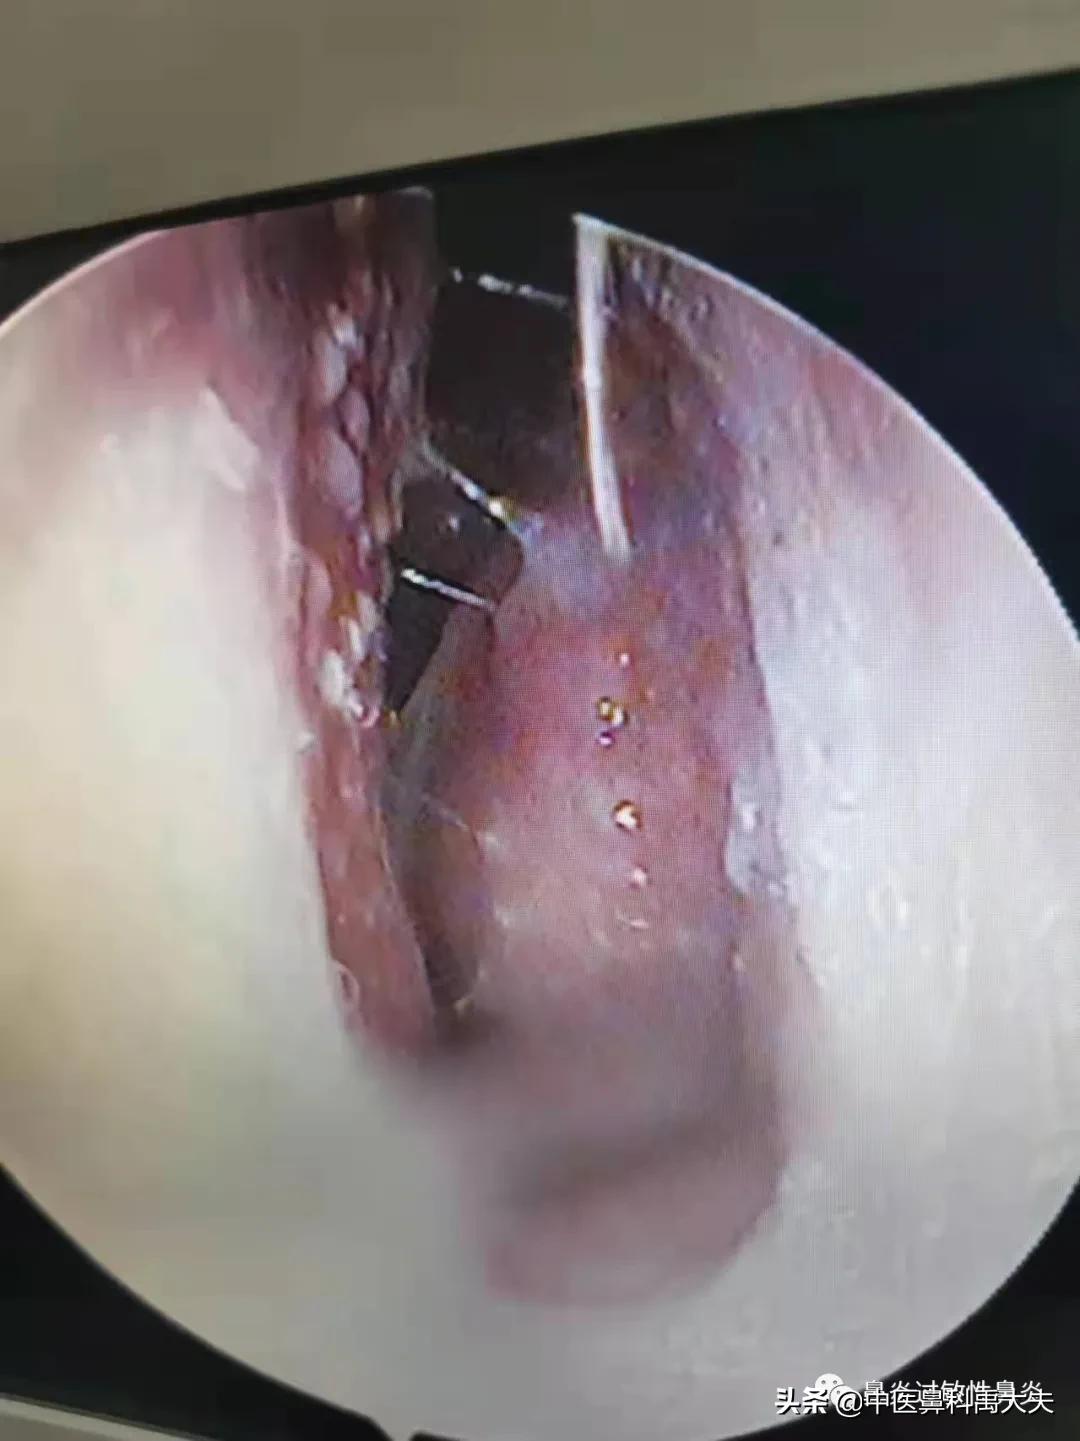

左侧鼻腔

鼻腔内窥镜检查可见下、中鼻甲肥大,鼻腔黏膜苍白,鼻中隔轻度偏曲,鼻中隔和鼻甲上伴有凸起样白色颗粒物;舌苔白腻水滑,伴有轻度口干口苦。具体舌苔图和鼻腔内镜图如下:

右侧鼻腔

冲洗后左侧鼻腔

冲洗后右侧鼻腔

经过我们的加盟客户一个冲洗护理,大家看看冲洗后的,情况,你就可能已经理解了,整体治疗中,为什么护理占到了三分之一的天下,通过冲洗后的对比,在这里就是呼吁大家对于鼻腔冲洗,我们一定要坚持去做,而且要养成一个良好的习惯。